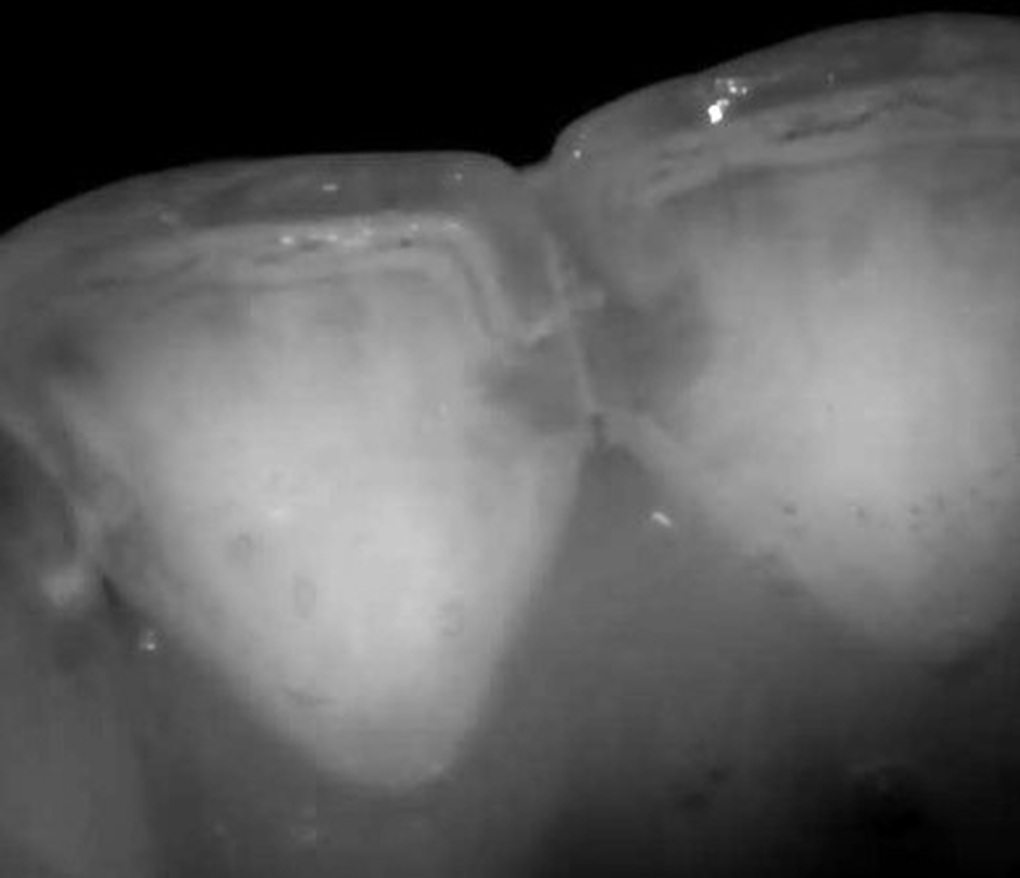

- Ánh sáng cận hồng ngoại (700-1.700 nm) không phải tia X mà vẫn xuyên qua men răng. Men khỏe cho ánh sáng truyền qua, men mất khoáng sẽ tán xạ mạnh, tạo hình ảnh tương phản rõ rệt giữa vùng lành và vùng tổn thương.

NIRI phát hiện sớm sâu răng mặt bên, kể cả khi X-quang cánh cắn không thấy được. Công nghệ này không bị nhiễu bởi mảng bám, nhuộm màu, không gây phơi nhiễm tia X, có thể chụp ảnh thời gian thực.

Hình ảnh sâu răng mặt bên nhìn thấy ở răng 11, 21 dưới ánh sáng cận hồng ngoại NIRI của máy quét trong miệng iTero Lumina pro (Ảnh: Nha khoa Như Ngọc).